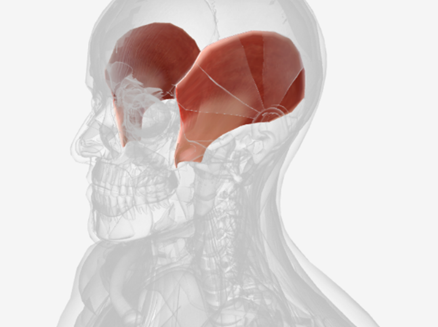

Temporalis

origin is the temporal and parietal bones of the cranium, coursing down and forward through the zygomatic arch, to insert on the coronoid process and the ramus of the mandible; function is to elevate the mandible and draw it back if protruded